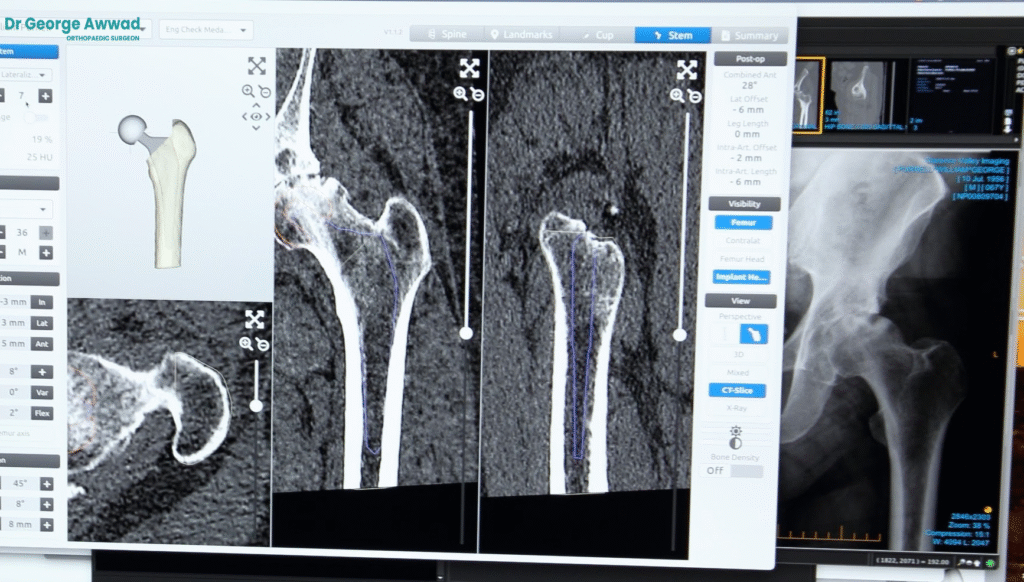

Digital 3D planning with MyHip software

Using specialised planning software (such as MyHip), Dr Awwad creates a 3D model of your hip based on the CT scan. This virtual model allows for precise pre-operative templating, helping to optimise:

- Joint alignment

- Leg length balance

- Implant fit and placement

This detailed plan is used to guide surgical decisions and supports consistent, personalised outcomes for each patient.

2. Imaging and surgical planning

Pre-operative planning plays a critical role in the accuracy and success of your surgery:

- X-rays assess joint space and alignment

- A CT scan is used to build a detailed 3D model of your hip

- MyHip digital planning software helps determine the best implant size, alignment, and positioning

This technology allows Dr Awwad to tailor the surgery to your anatomy before entering the operating theatre.